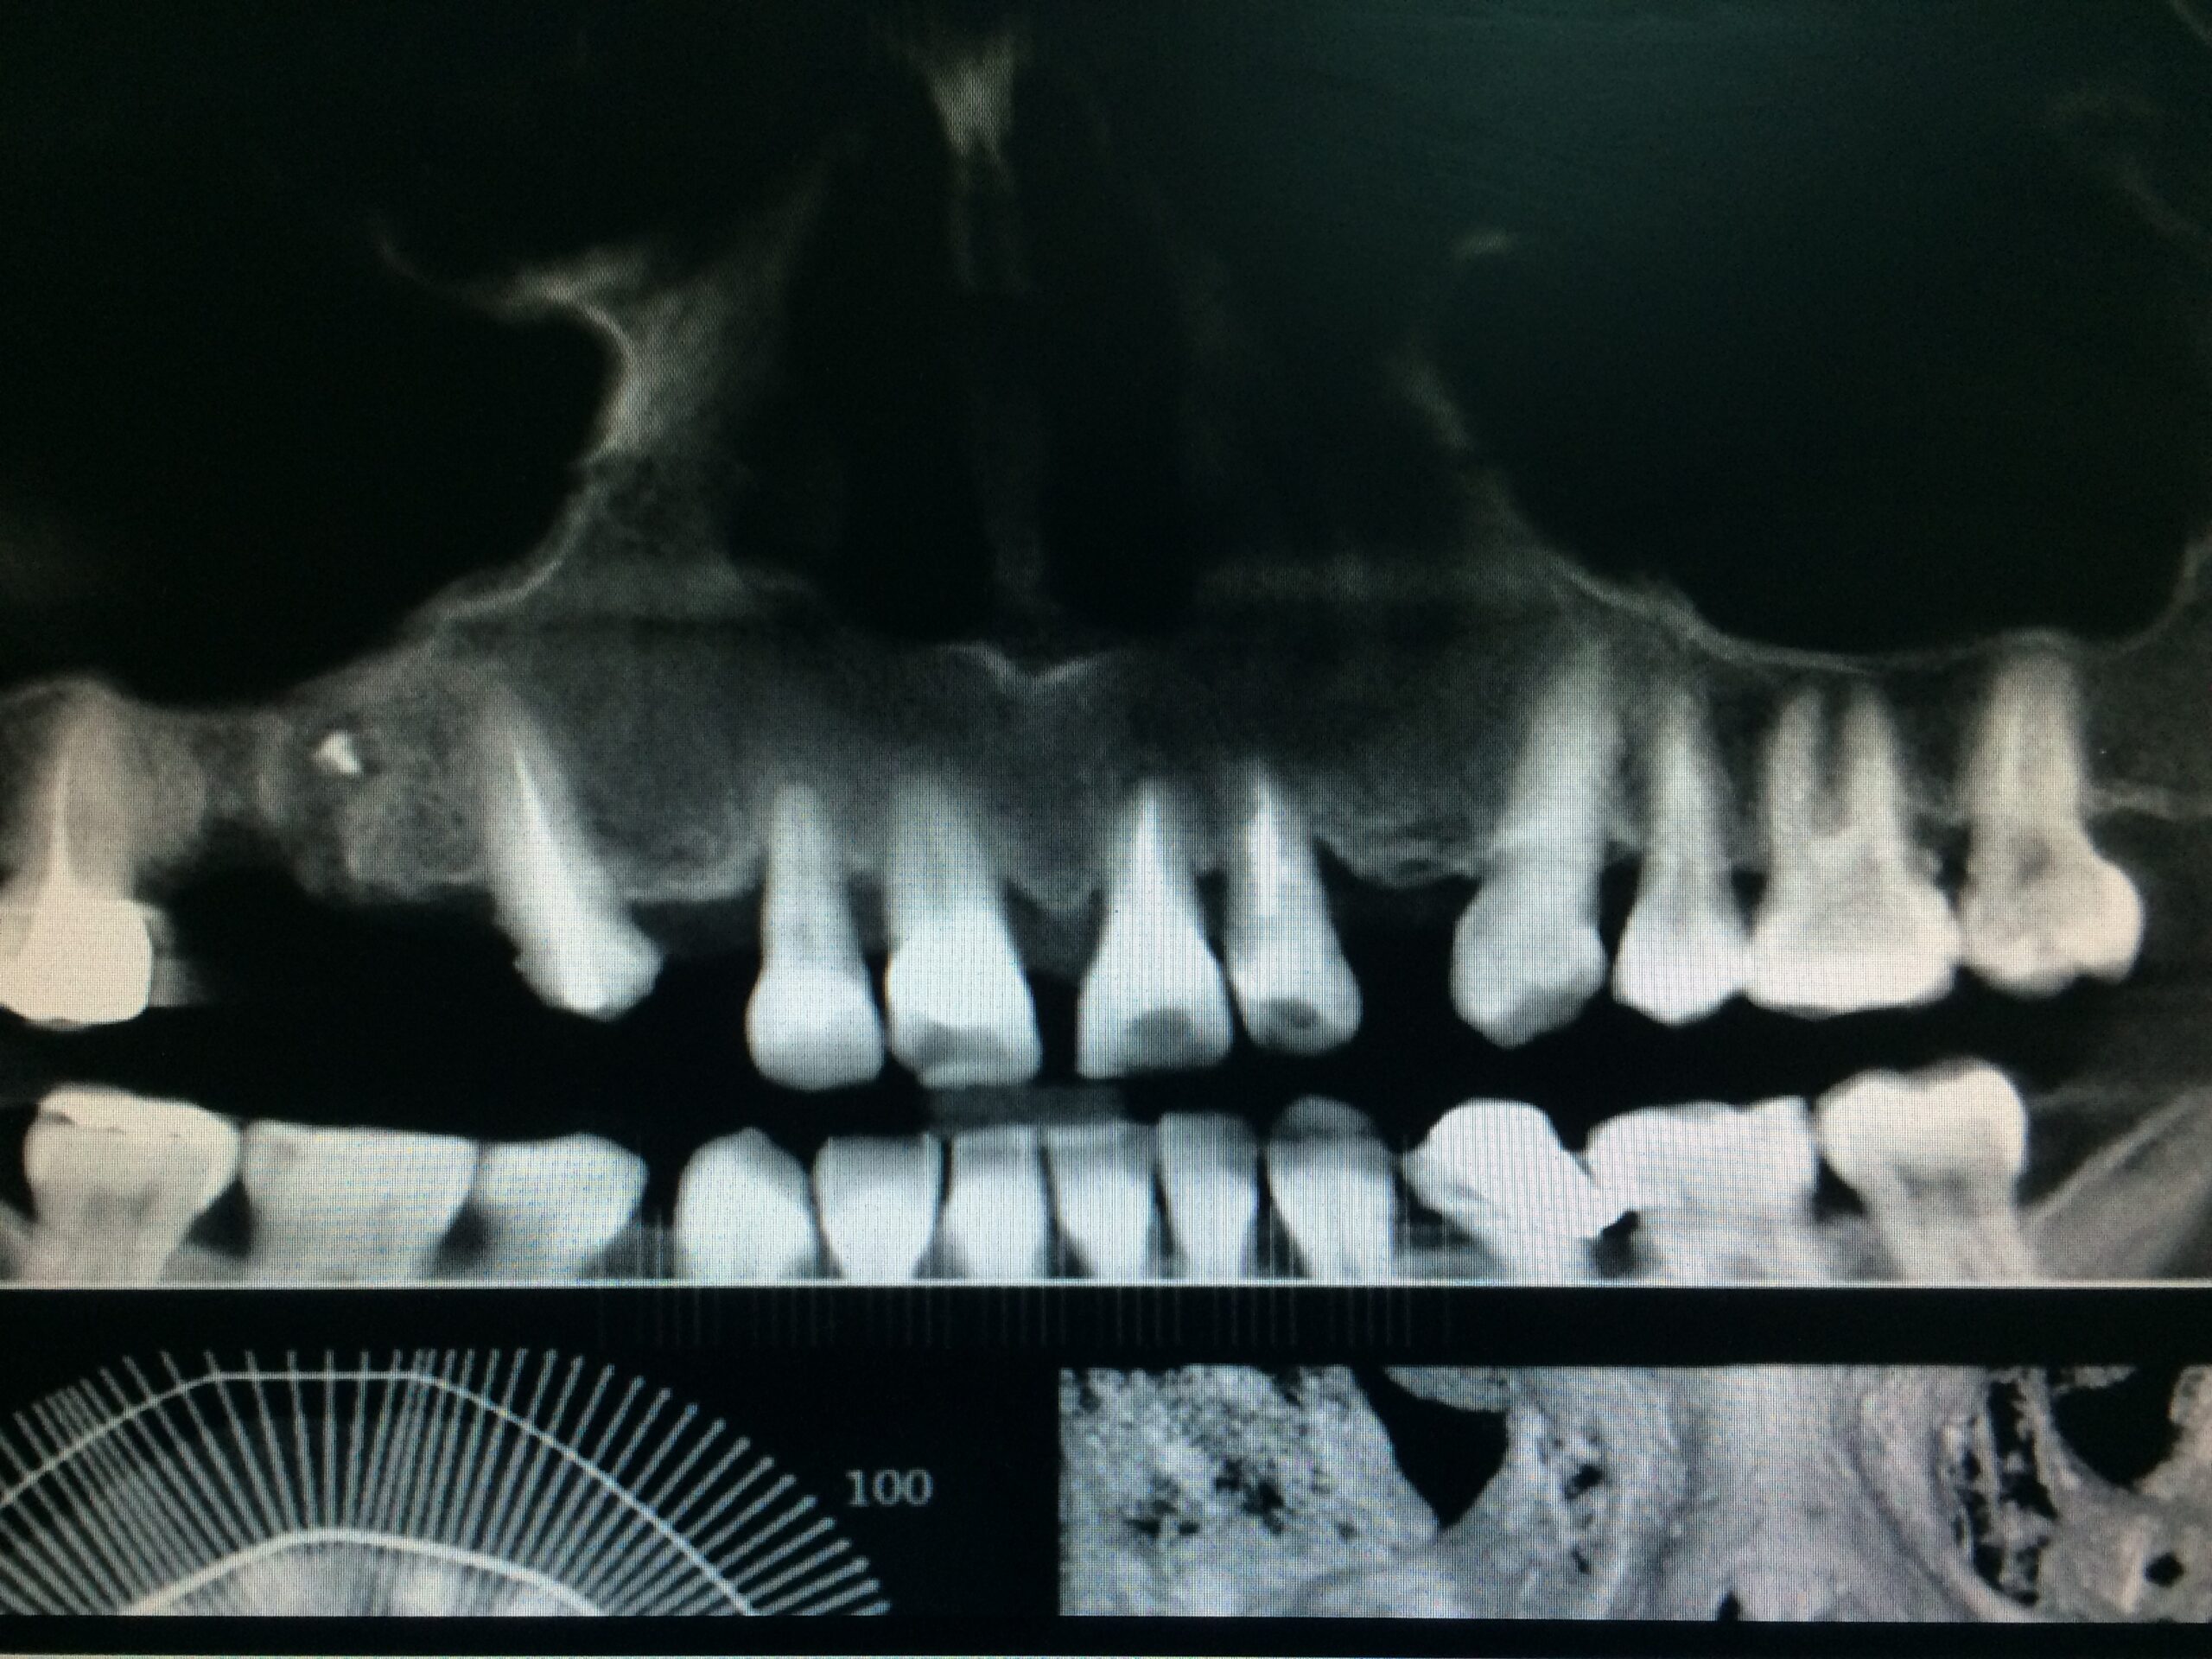

→ Avant l’intervention

Après une étude approfondie de vos antécédents dentaires et médicaux, le dentiste détermine si les implants dentaires sont indiqués dans votre cas. Il examine ce qui doit être fait, se prépare et vous explique en plan de traitement à venir.

La durée totale du traitement dépend de plusieurs facteurs. Il est déterminé en fonction du nombre de dents à remplacer, du volume osseux, de l’état général du patient. En général, il faut entre 3 et 9 mois.